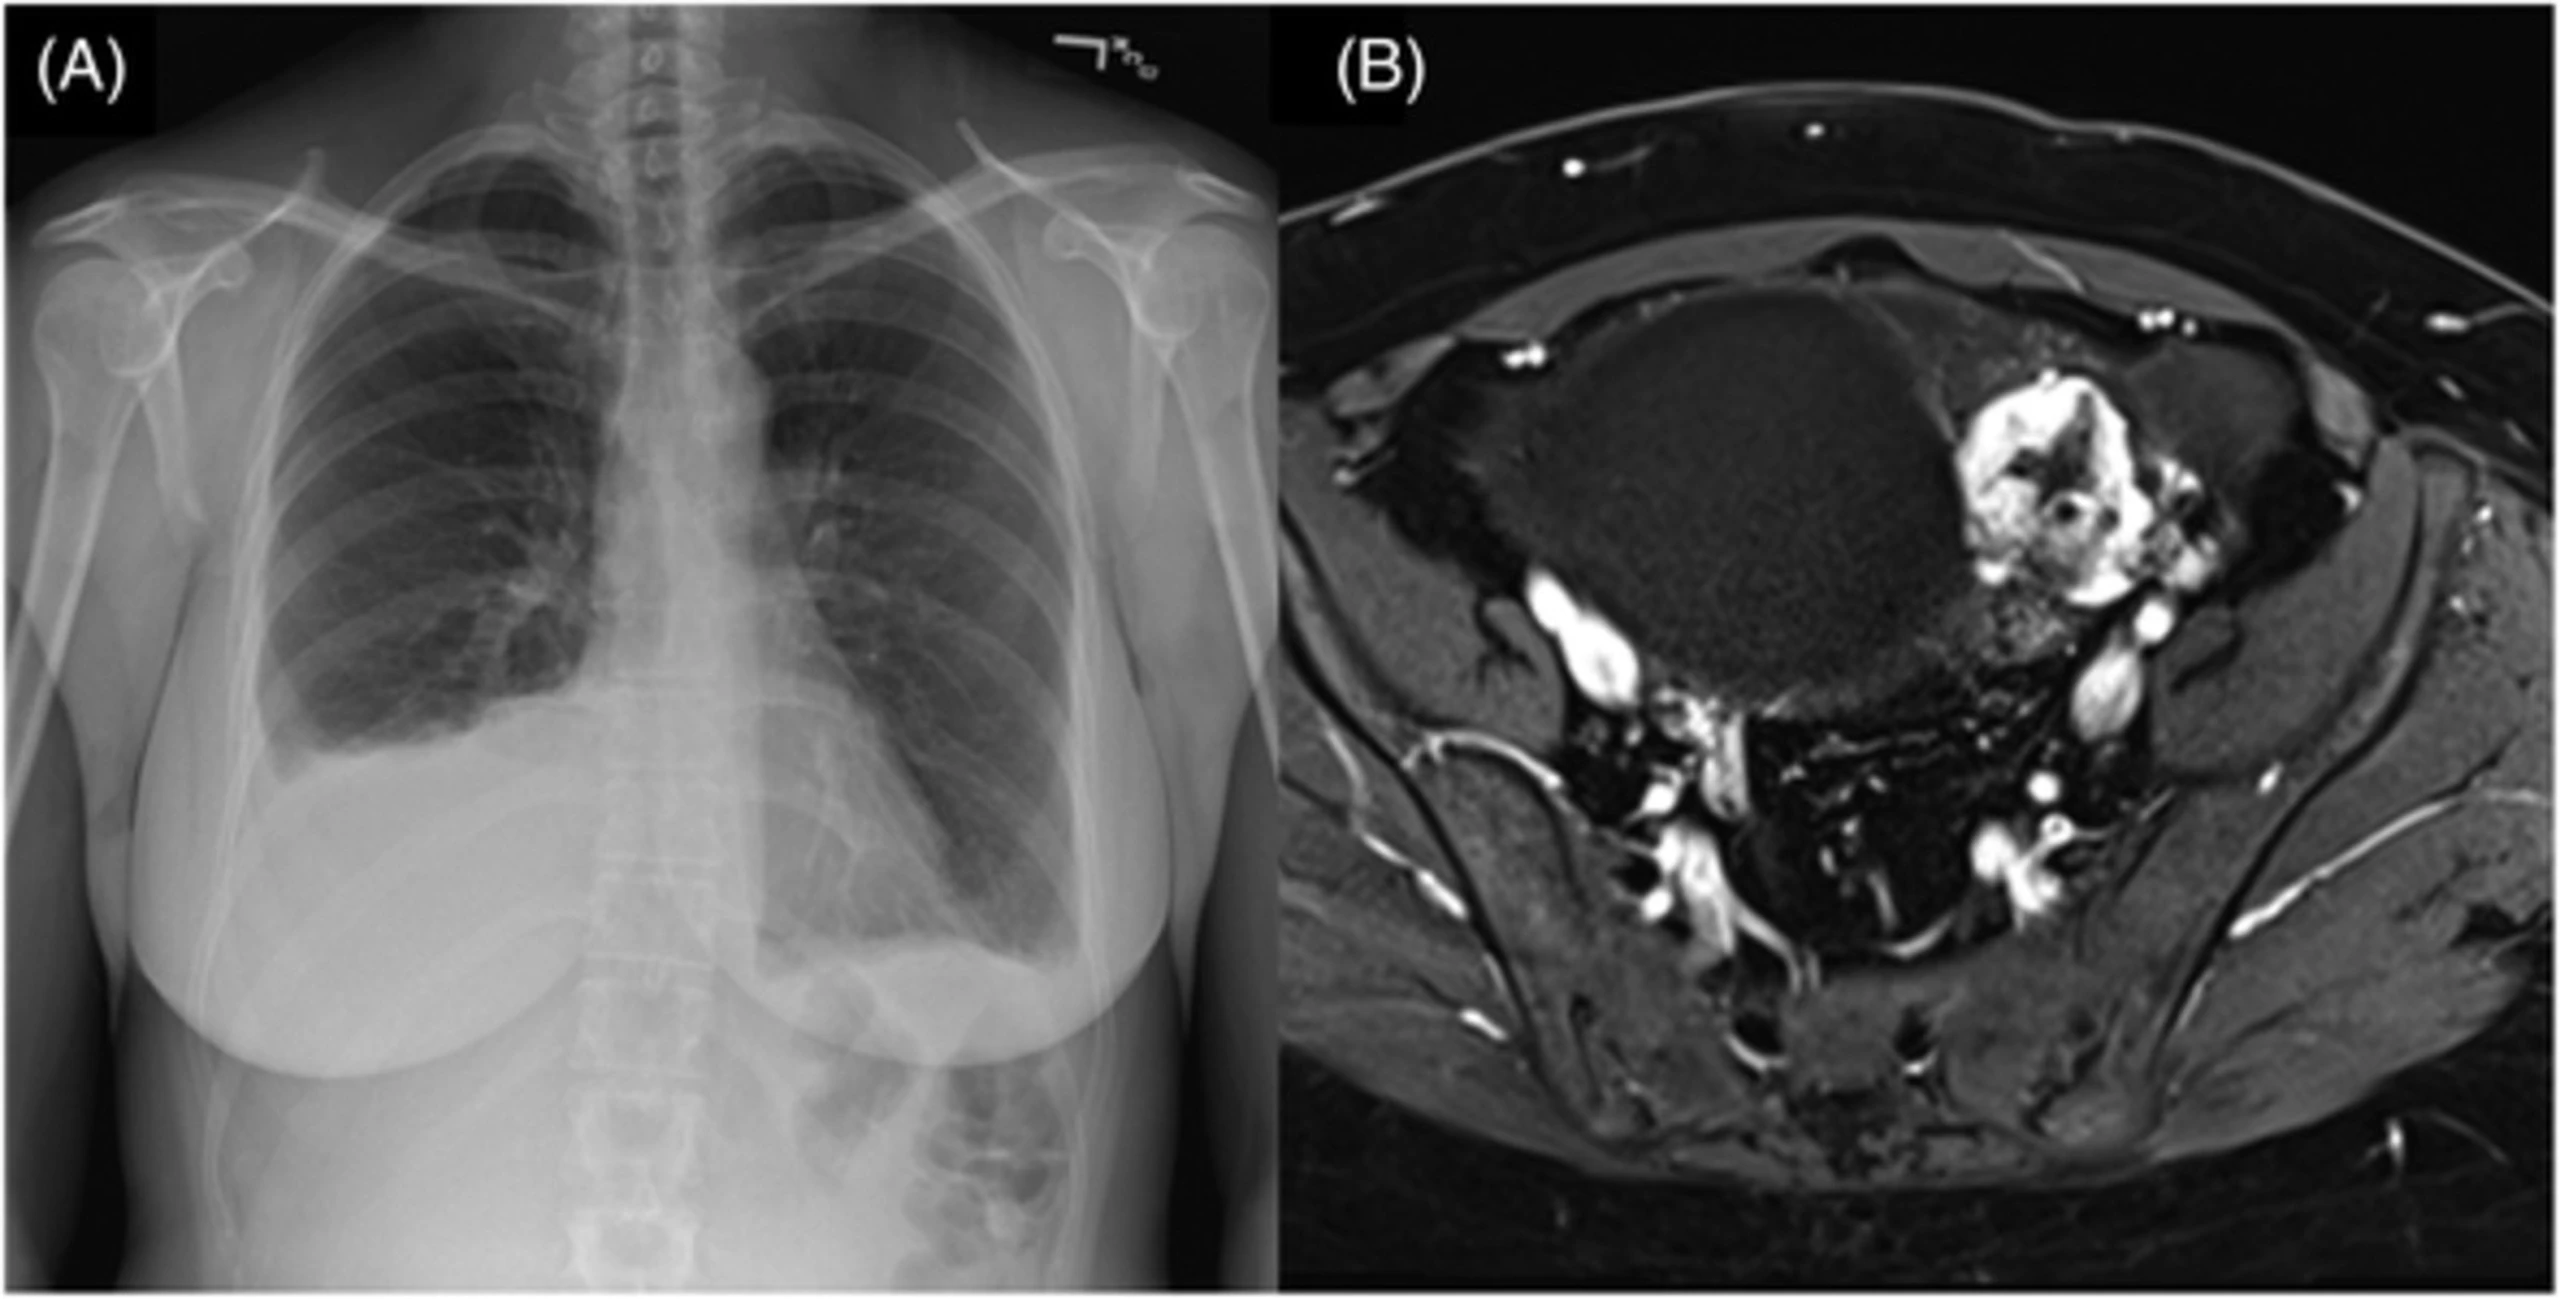

Các xét nghiệm chẩn đoán: